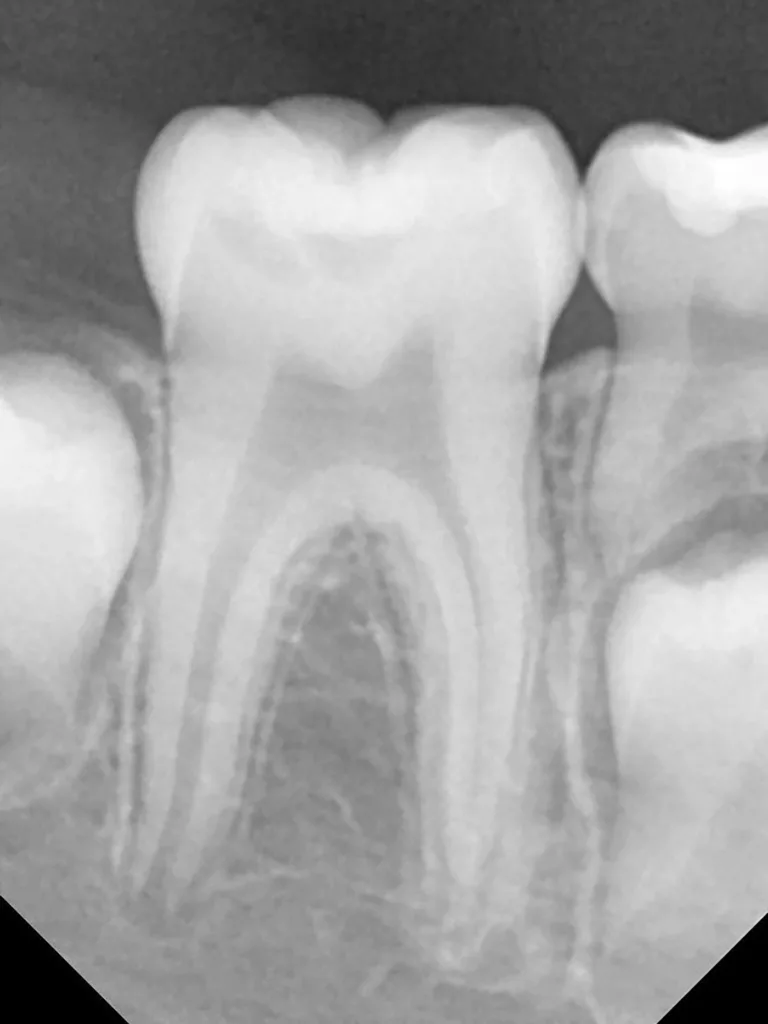

Im Rahmen der jährlichen Kontrolluntersuchung wurde bei einem achtjährigen Mädchen auf der routinemäßig angefertigten Röntgenaufnahme eine mittelgroße PEIR des Zahnes 46 (Grad 2 der Läsion nach Seow) entdeckt (Abb. 43). Die Patientin war komplett beschwerdefrei und der Zahnschmelz des betroffenen Zahnes sah intakt aus (Abb. 44 und 45). Weil auch hier der PEIR-Defekt gräulich durchschimmerte (Abb. 44 und 45) und der Zahn bereits seit einem Jahr durchgebrochen war, entschieden wir uns in diesem Fall, den Defekt klassisch mit Komposit zu restaurieren. Unter Lokalanästhesie mit Septanest 1/100 000 (Septodont, Frankreich) wurde zunächst Kofferdam mithilfe der Klammer U67 (KSK Dentech, Japan) gelegt (Abb. 45). Weder visuell noch mittels Sondierung konnte eine Verbindung zur Läsion festgestellt werden. Deswegen wurde an der Stelle, an welcher der PEIR-Defekt gräulich schimmerte, intakter Zahnschmelz der lingualen Querfissur entfernt (Abb. 46). Innerhalb der Läsion wurde nekrotisches intrakoronales Weichgewebe vorgefunden (Abb. 47), das problemlos mittels RONDOflex plus 360 (KaVo Dental, Deutschland) mit dem 27-µm-Pulver vollständig entfernt werden konnte. Der Boden des Defektes zeigte eine glatte, runde Form sowie helles, hartes und intaktes Dentin. Eine Präparation war nicht erforderlich, es wurde lediglich die Zahnschmelzkante geglättet (Abb. 48). Für die Restauration kamen erneut das Adhäsiv Optibond FL (Kerr, USA) und das Komposit Estelite ASTERIA OCE, A2B und Universal Flow AO2 (Tokuyama, Japan) zur Anwendung (Abb. 49). 6 Monate nach der Behandlung zeigte sich das Ergebnis sowohl aus klinischer als auch radiologischer Sicht stabil wie die Abbildungen 50 und 51 zeigen.

Fall 5